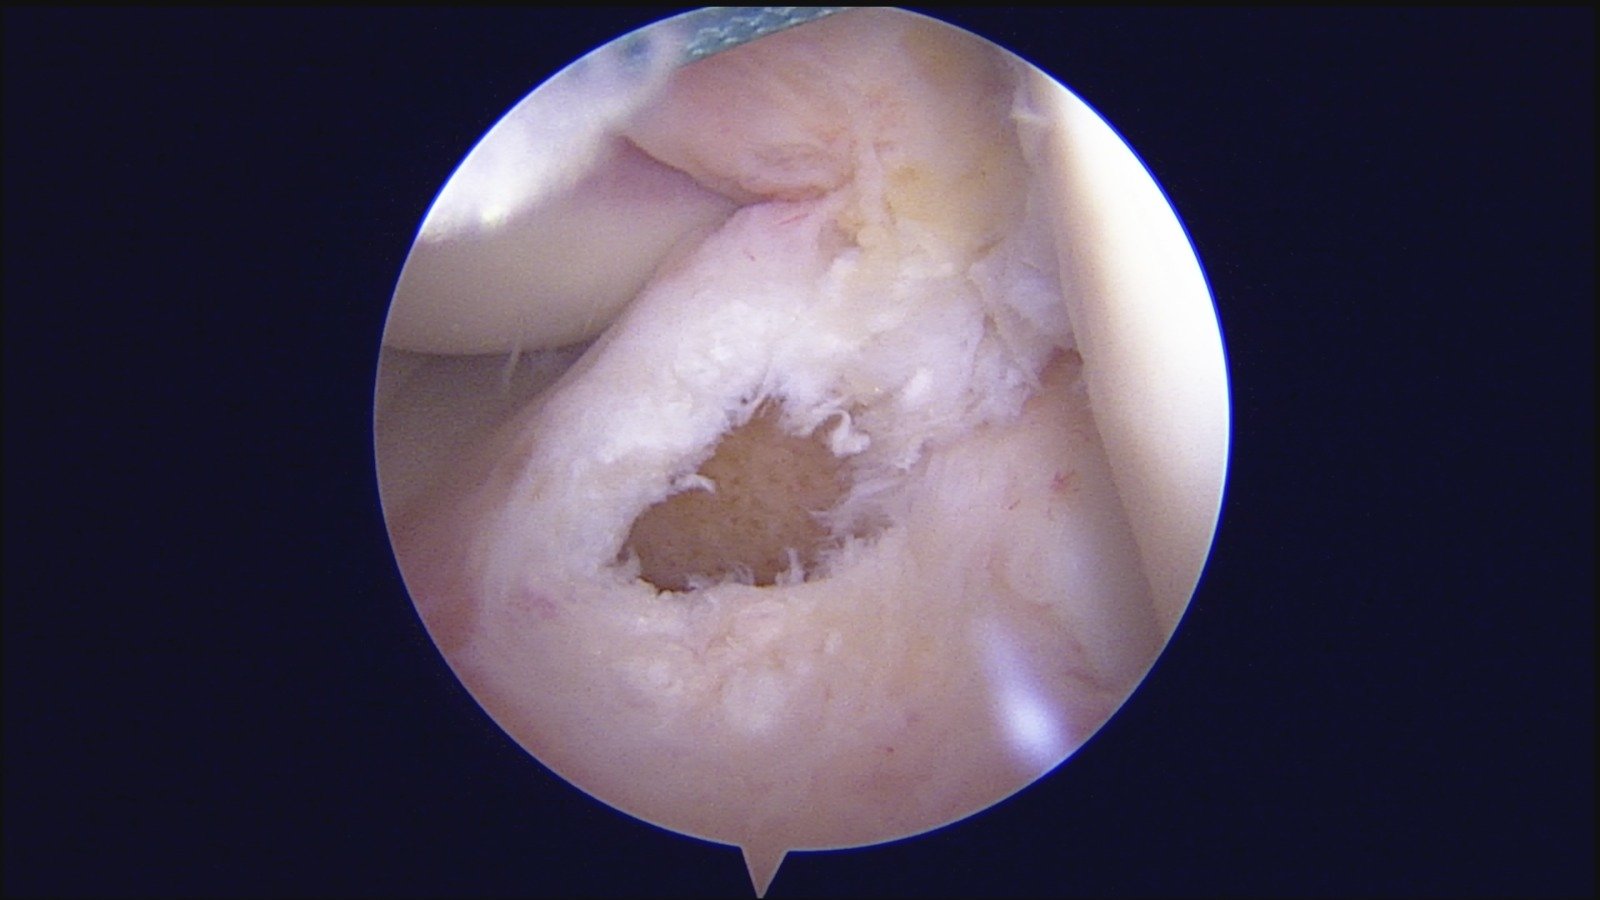

GalleryShoulder rotator cuff repair Meniscus root repair Meniscus repair Bankart repair for recurrent shoulder dislocation ACL reconstruction Machines Instruments